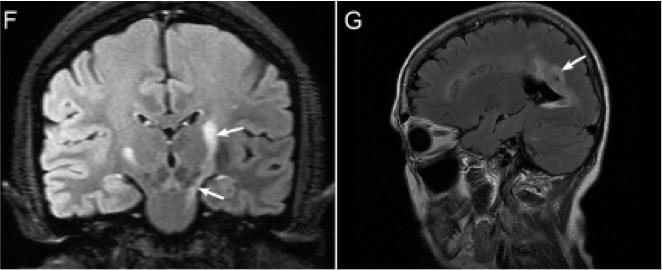

4. NMOSD 头MRI:丘脑、三脑室周围、锥体束和侧脑室周围等部位都可能出现片状、云雾状病灶